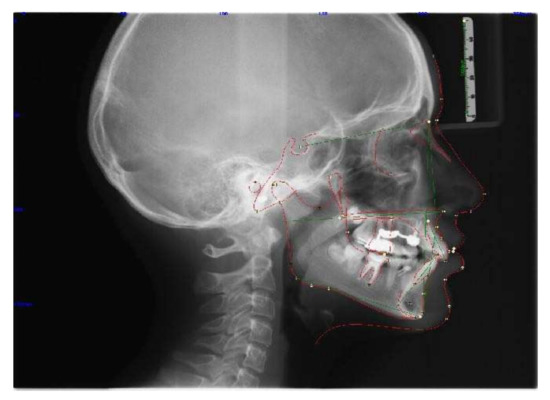

A 11-year-old patient presented to the private practice with her parents with a chief complaint of an unattractive smile, mainly due to an upper canine. The facial analysis showed an hypodivergent facial type with a reduced lower-third of the face, a convex profile with mandibular retrusion and upper lip protrusion with a proper nasolabial angle (Figure 1). The mini-esthetic analysis showed a superior inter-incisive line not coinciding with the median of the face, migrated on the left side, a ratio between arch amplitude and amplitude of the smile in the norm, and a reduced exposure of the smile with an irregular and asymmetrical smile arc. The intraoral clinical analysis revealed sagittal relationships of molar class II and canine class II, an upper interincisive line migrated on the left side, decreased transversal development of the upper arch, a severe crowding in the upper arch with a lack of space for 1.3 alignment, a 6.5 mm overjet, a 3.5 mm overbite, and an increased Spee curve (Figure 1 and Figure 2). The patient asked for treatment because the upper right canine (UR3) was not aligned and ectopic in the upper arch. Panoramic radiography and lateral cephalogram were required to confirm the diagnostic hypothesis of class II malocclusion and to measure incisors proclination. The cephalometric analysis showed a skeletal class II, hypodivergence and proclination of the upper and lower incisors (Figure 3, Table 1 and Table 2).

Figure 3.

Pretreatment radiographs and cephalometric analysis.

Figure 5.

Radiograph post Herbst and cephalometric analysis.